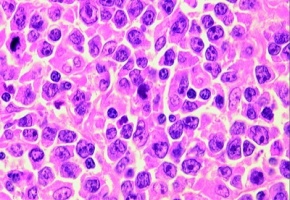

Enfin une bonne nouvelle concernant le Covid. Des chercheurs ont en effet montré que l’immunité cellulaire (via les lymphocytes T CD8) développée à la suite d’une infection par le Sars-CoV-2 resterait efficace contre les différents variants actuellement en circulation, contrairement à l’immunité humorale, dont plusieurs études ont montré qu’elle diminuait vis-à-vis des variants sud-africains et brésiliens (nécessité d’un taux d’anticorps plus élevé pour neutraliser le virus).

Pour cette étude in vitro menée par les Instituts nationaux de santé américains (NIH) et l'Université Johns Hopkins, des échantillons sanguins ont été prélevés sur 30 personnes ayant contracté le virus avant l'émergence des variants. Ils ont ensuite été mis en contact avec les différents variants. L’objectif était de savoir si les lymphocytes CD8 étaient capables de reconnaître les trois variants majeurs du Sars-CoV-2: le B.1.1.7 (apparu en Angleterre), le B.1.351 (identifié en Afrique du Sud) et le B.1.1.248 (signalé au Brésil). Les auteurs ont alors montré que la réponse de ces « cellules tueuses » restait majoritairement intacte et que les CD8 pouvaient reconnaître pratiquement tous les variants. Ils restent cependant prudents, estimant que des études plus larges sont nécessaires pour confirmer ce résultat.